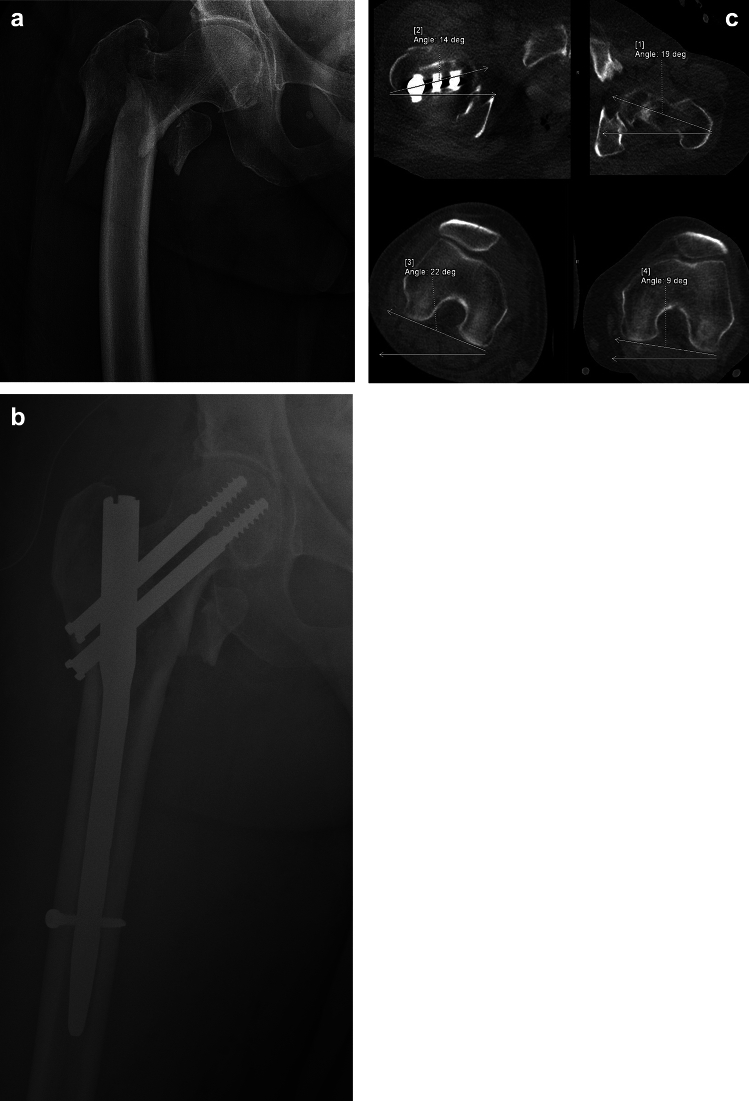

Materials and methods: We conducted a prospective study focused on closed reduction in intramedullary nailing of trochanteric fractures (AO 31A1-3) in 100 consecutive patients and its influence on final malrotation. Immediately after the closed reduction, the rotation of affected limb was measured using a balanced goniometer and the values were compared to the postoperative CT calculation. Final femoral malrotation exceeding 15° was considered significant. All results were statistically analyzed.

Results: In total we observed femoral malrotation exceeding 15° in 33 patients (33.3%). Internal rotation was significantly more common than external rotation (31 vs. 2 patients). Intraoperative rotation up to 15° resulted in a malrotation of 10.3% (3/29 patients). When limb rotation on the traction table exceeded 20°, malrotation incidence increased to 51.0% (26/51 patients), making this fixed position a risk factor for significant femoral malrotation (p = 0.0076). General anesthesia was also associated with a significantly higher rate of malrotation compared to spinal anesthesia (p = 0.0154), however we did not find any statistical difference in error rates based on patient BMI or physiological femoral neck ante-version.

Conclusions: Our findings underscore the significant risk of femoral malrotation associated with perioperative rotations beyond 20°, emphasizing the need for precise rotational control during surgery. Excessive rotation on the traction table in an attempt to achieve better fracture alignment significantly increases the risk of femoral malrotation.